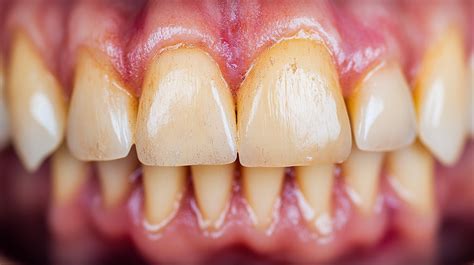

- Decoloración: Cambio de color de los dientes: Con la erosión dental se va perdiendo el blanco inicial de nuestra dentadura. Los dientes pueden parecer amarillentos, ya que la dentina (la capa que se encuentra debajo del esmalte) queda más expuesta.

- Cambios en la forma de los dientes: Dientes que se ven más pequeños, achatados o con superficies planas que antes no tenías. Los huecos en los dientes y el desgaste general de la superficie de los dientes y los bordes de mordida son signos comunes de erosión.

- Transparencia: Transparencia: los incisivos pueden parecer transparentes cerca de los bordes con los que muerdes.

- Grietas y hendiduras: Grietas y hendiduras: si el esmalte dental empieza a erosionarse, los dientes pueden presentar pequeñas grietas y hendiduras en la superficie masticatoria.